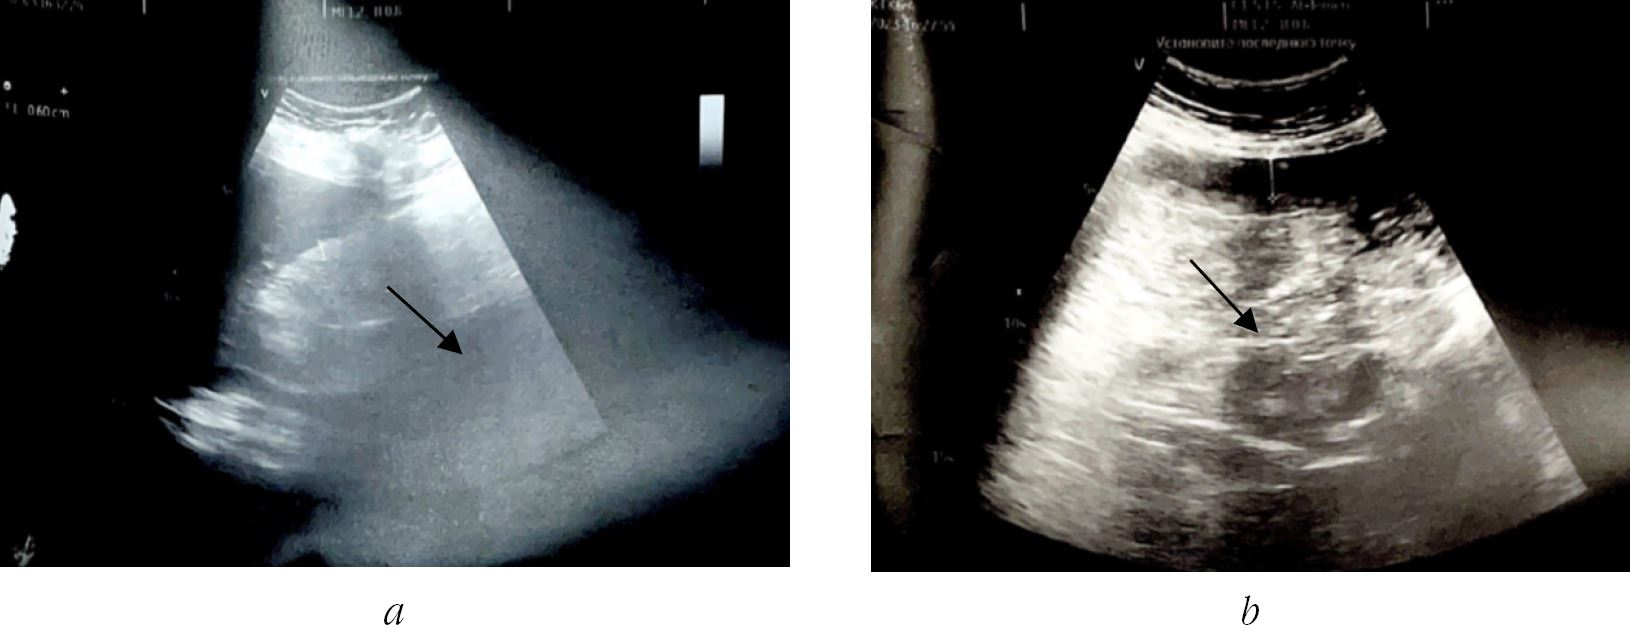

On the 10th day of the postoperative period, according to CT scans of the abdominal cavity, there was a picture of acute pancreatitis with pronounced infiltrative changes in the parapancreatic tissue. A pseudocyst of the tail of the pancreas was formed (Fig. 2).

Fig. 2. CT scan of acute pancreatitis with infiltrative changes in the parapancreatic tissue. Pseudocyst of the tail of the pancreas (indicated by arrows)